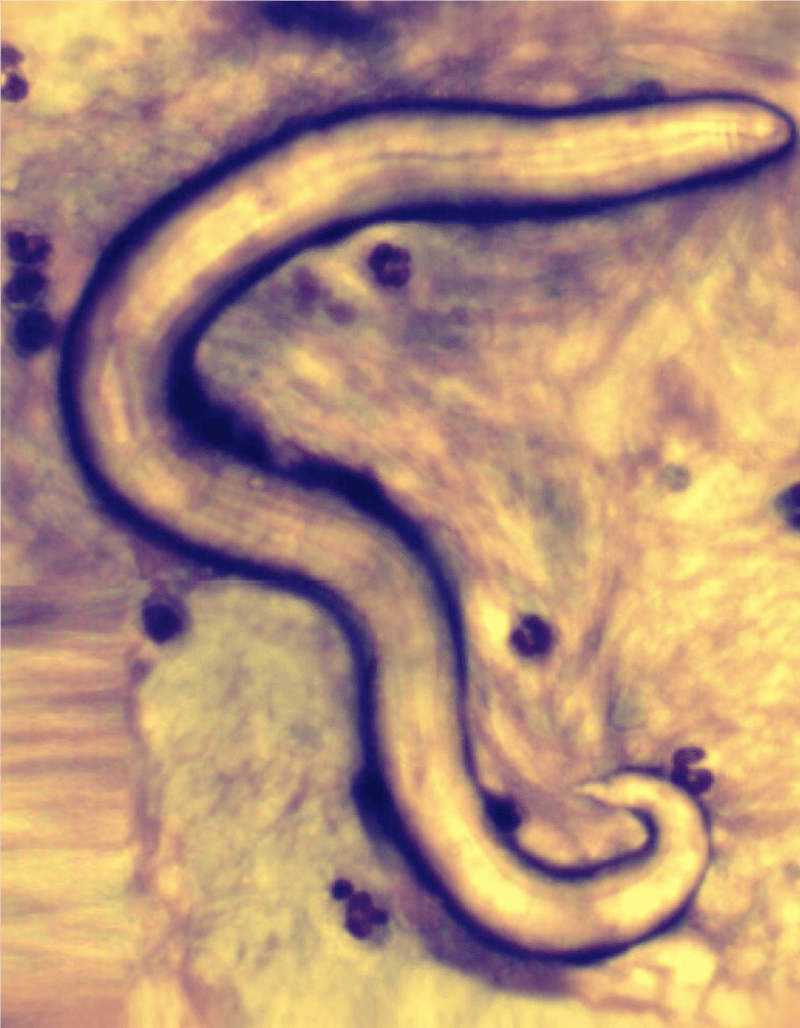

Lungworm infections are usually caused by Oslerus Osleri also known as tracheal worms. These parasites cause infection and heavy breathing. They create lung inflammation, needing medical attention.